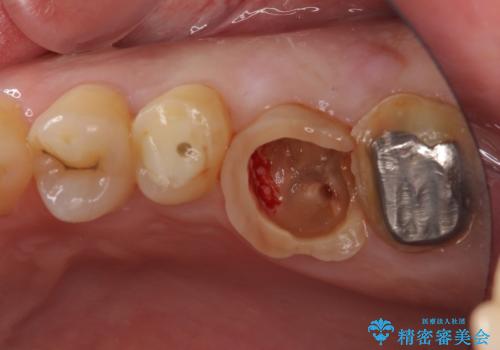

- 長い間虫歯を放置しており、違和感を感じ始めてきたので治療を開始したいと来院された患者様です。

極力抜歯が回避する方法を選択して診察を開始しましたが、1本は保存困難と判断されたため、フルジルコニアブリッジによる補綴治療を行うこととしました。

歯根の先端に病変の認められた奥歯は、補綴前に根管治療を行うこととしました。

違和感を感じていた歯は虫歯が非常に大きく、骨に到達するほどの穴が空いていました。